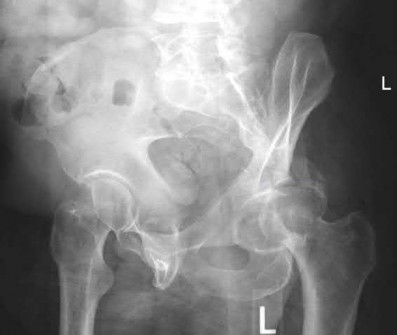

A 27 year-old patient sustains a fracture-dislocation of the acetabulum. Pelvic radiographs (Figures A and B) are taken at initial presentation and a CT scan (Figures C and D) is performed after reduction of the hip in the emergency room. What is the importance of the finding highlighted in the CT scan cuts?

The CT images shown in Figures C and D display significant marginal impaction of the joint surface.

Marginal impaction is common in posterior wall fractures and fracture-dislocations. Critical review of CT imaging of posterior wall fractures can help with preoperative planning for identifying impaction of the articular surface of the acetabulum. Restoration of the sphericity of the acetabulum to match that of the femoral head is important for successful outcome following ORIF of posterior wall fractures. A common surgical technique to accomplish joint surface restoration includes freeing the impacted articular segments, bone grafting of the void created to support the articular segments, and buttress plating of the posterior wall fracture fragments.

Figures A and B are radiographs of the posterior wall fracture and hip dislocation. They do not show the large amount of marginal impaction of the acetabular surface. Figure C (coronal reconstruction) and Figure D (sagittal reconstruction) point out a large a amount of marginal impaction of the acetabular. Note the disruption of the joint surface on the intact portion of the acetabulum.